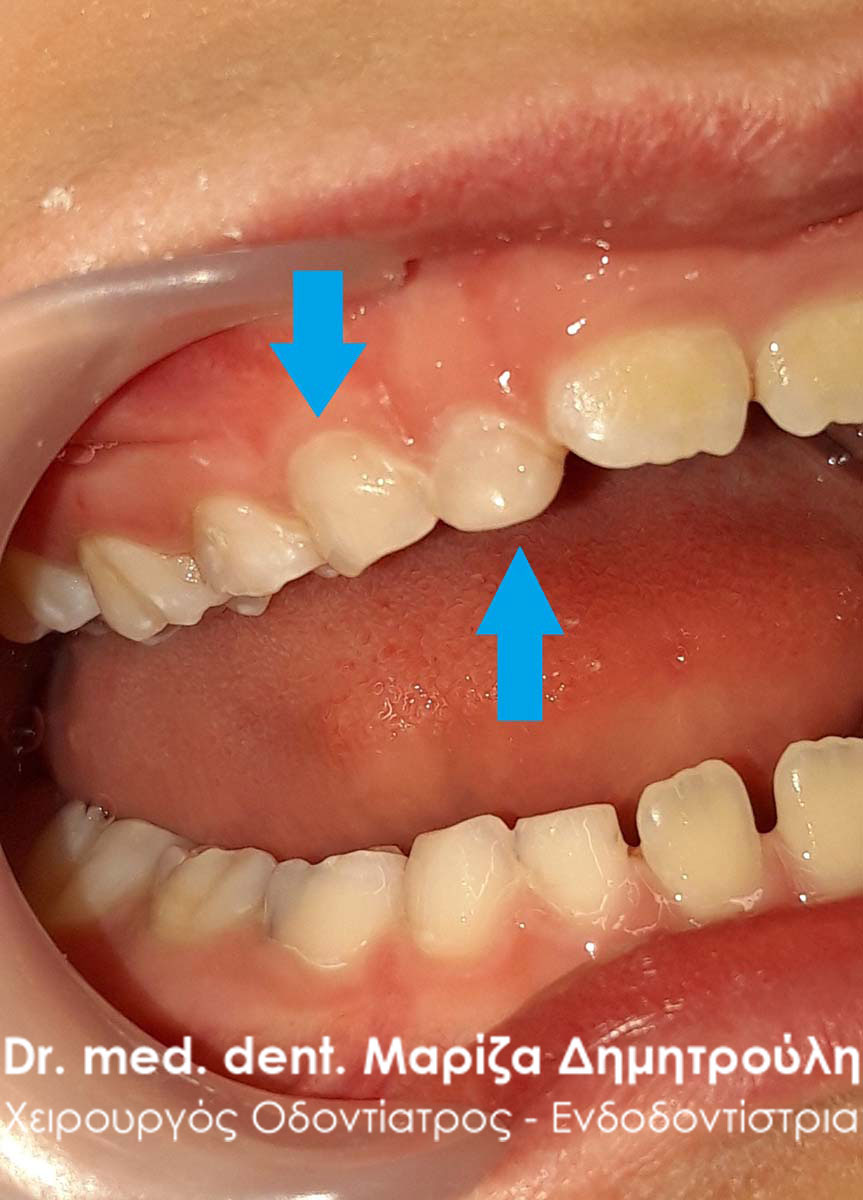

Επίσης στην πρόσθια περιοχή της άνω γνάθου παρατηρήθηκε ένα μικρό συρίγγιο στην περιοχή του πρώτου αριστερού νεογιλού γομφίου, ο οποίος είχε έντονη κινητικότητα χωρίς όμως να “πέφτει”. Στην περίπτωση αυτή ήταν απαραίτητη η εξαγωγή του νεογιλού δοντιού, γιατί το παιδί είχε το συρίγγιο τουλάχιστον τις τελευταίες 3 εβδομάδες (σύμφωνα πάντα με τα λεγόμενα της μητέρας). Με την εξαγωγή του δοντιού το συρίγγιο υποχώρησε τις επόμενες μέρες και το παιδί ανακουφίστηκε.

Συρίγγιο στην περιοχή του πρώτου νεογιλού τομέα